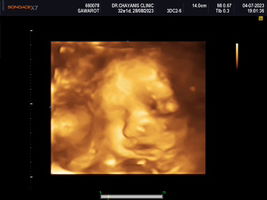

กำลังตั้งครรภ์